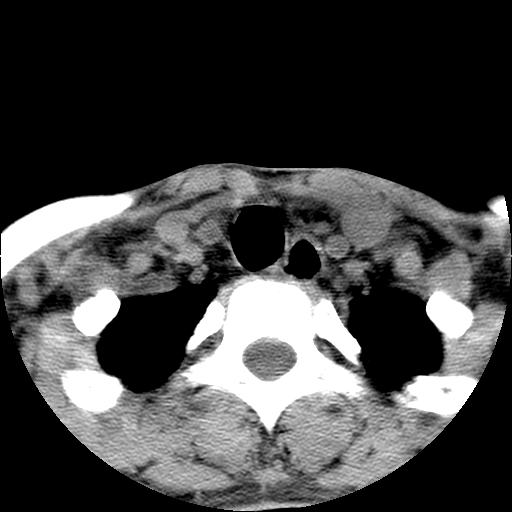

标题: CT15118:f-27y,左颈部肿一个月,无发热、无压痛 [打印本页]

标题: CT15118:f-27y,左颈部肿一个月,无发热、无压痛

1、甲状腺左叶病变:腺瘤?结节性增生?其他?

2、上极周围间隙病变。

3、2者关系?

左侧甲状腺肿大,密度不均.同侧甲状软骨似有破坏(建议传骨窗).左侧颈静脉增粗,各组织之间分界不清,有多个肿大淋巴结.甲状腺肿并感染?临床症状不符.淋巴结核?请结合其他检查.